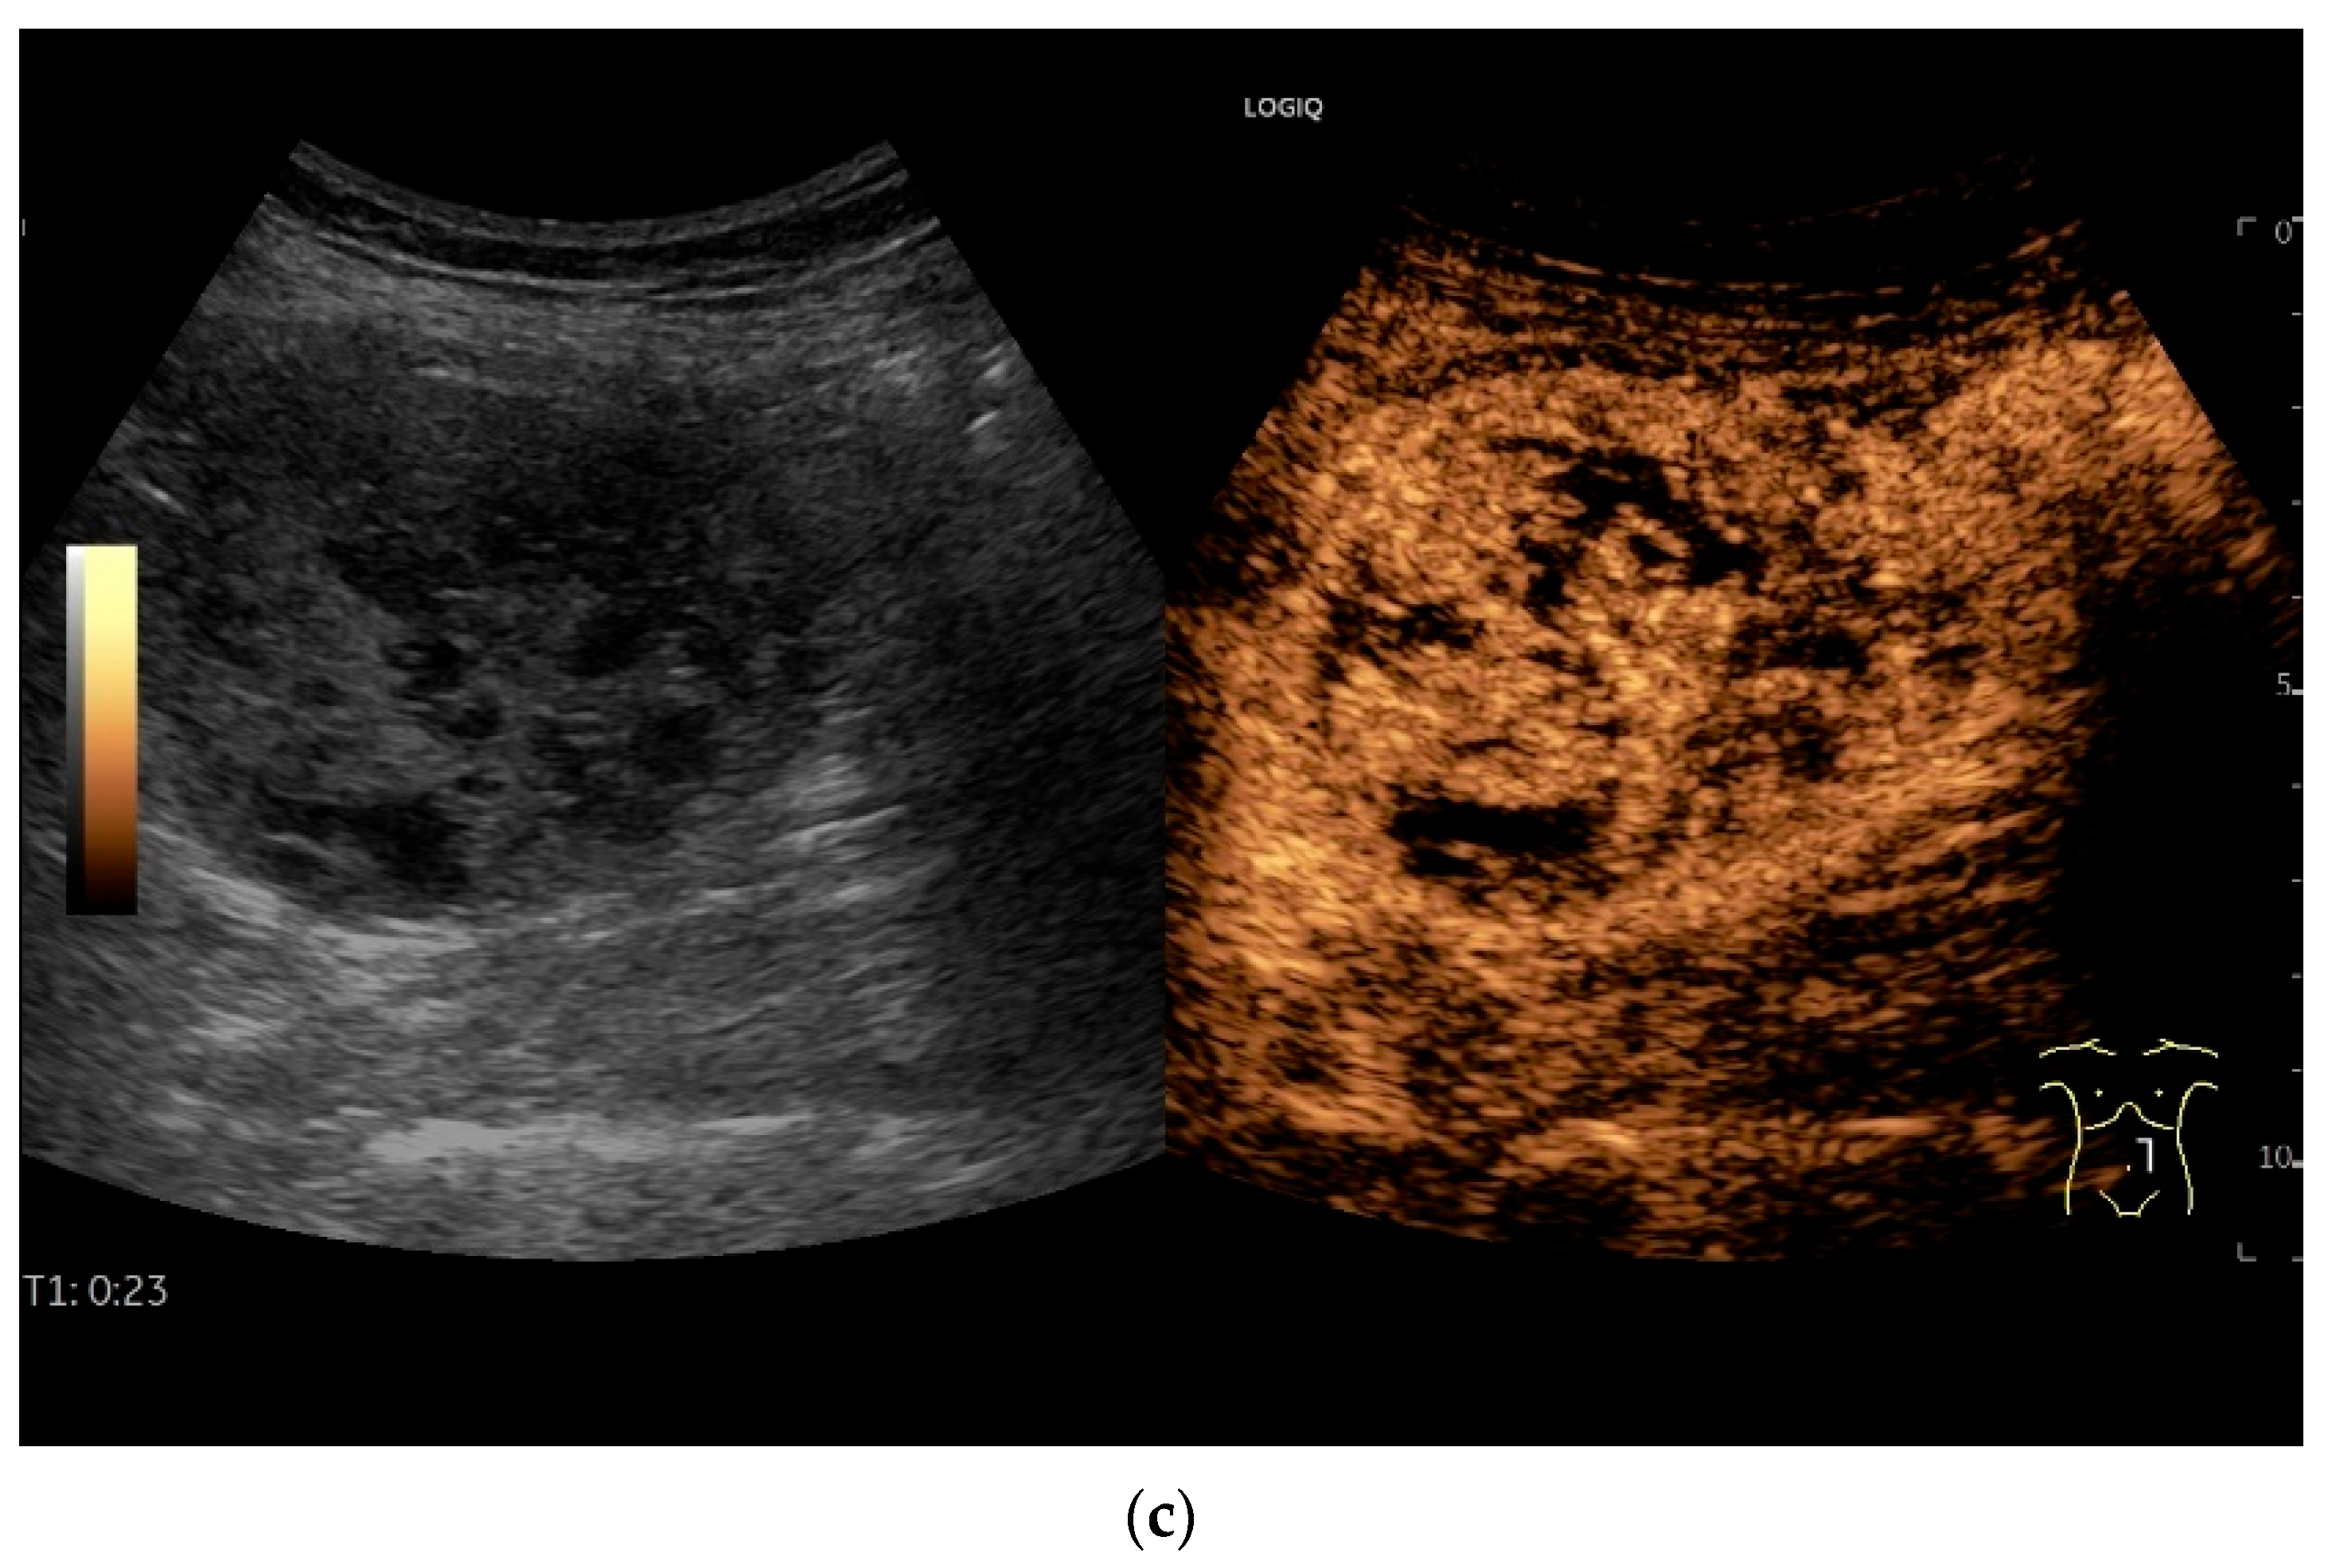

4.6. CEUS

- Multiparametric US, including CDI and CEUS, enhances lesion characterization by assessing vascularity and necrosis, especially in GISTs and neuroendocrine tumors.

- Cui, N.Y.; Gong, X.T.; Tian, Y.T.; Wang, Y.; Zhang, R.; Liu, M.J.; Han, J.; Wang, B.; Yang, D. Contrast-enhanced ultrasound imaging for intestinal lymphoma. World J. Gastroenterol. 2021, 27, 5438–5447. [Google Scholar] [CrossRef]

| Lymphoma | Very pronounced wall thickening with marked hypoechogenicity. Large regional and distant lymph nodes. Look for splenic infiltration. Tumor vessels on CDI and hyperenhancement on CEUS. Heterogeneous hyperechogenicity of the mesentery with walling of the mesenteric vessels. Multiple localizations are possible. |

| GIST | Round hypoechoic masses, homogeneous or heterogeneous depending on size. They usually originate from the muscularis propria, which can be difficult to distinguish in US. Small vessels on CDI, hyperenhancement on CEUS. They move with the small intestine and can change position. |